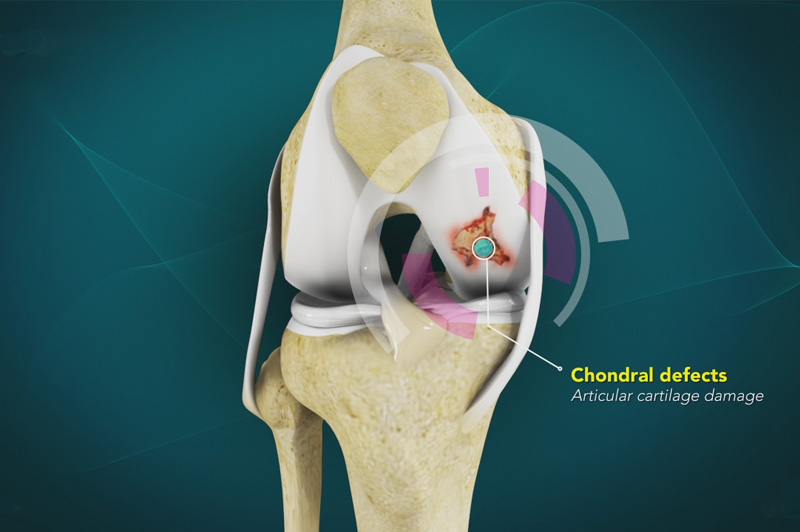

Articular cartilage is the smooth, white tissue that covers the ends of bones where they come...